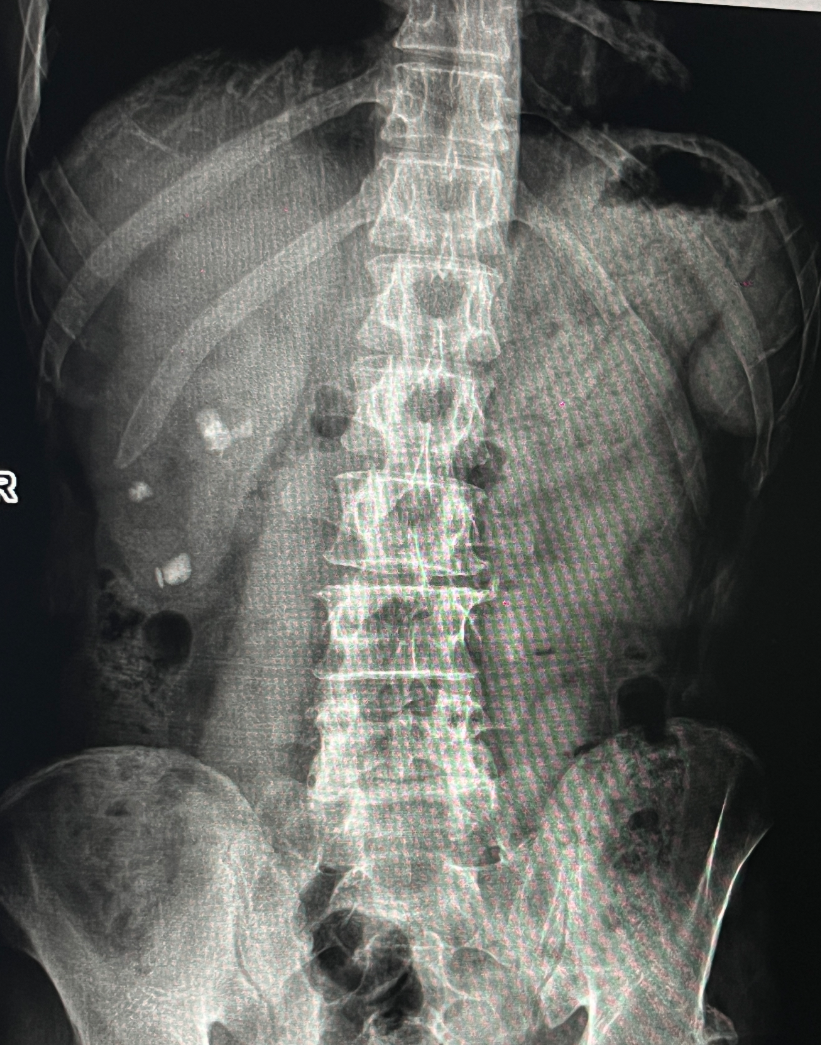

该患者因“左侧腰腹部间断性疼痛5天”入院。入院后,经过系统的泌尿系CT、超声及实验室检查,临床诊断为“双肾输尿管结石并积水和感染”。影像资料显示,其右侧肾脏结石体积较大,左侧输尿管结石已造成梗阻并引发感染,病情存在一定复杂性。